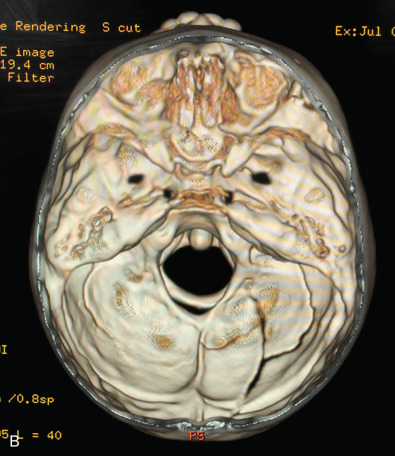

Plain films of the craniofacial skeleton, especially the midface, are of no use in the assessment of facial trauma in the pediatric population. Developing sinuses and tooth buds may obscure already overlapping planes. Computed tomography (CT) scans are necessary in order to accurately diagnose pediatric facial trauma. Fine facial cuts are necessary to adequately define facial fractures, and 3D reconstructions can be extremely useful in planning surgical intervention and teaching trainees. Cone beam CT scans and orthopantomograms (panoramic radiographs or panorex) are also useful to assess for dental injuries.

Facial fractures in children are often less displaced than those of adults and greenstick fractures are common given their more flexible bones with more mobility at suture lines and less bone mineralization. The bone exhibits a higher cancellous-to-cortical bone ratio, and without the development of the air-filled paranasal sinuses which affect the compliance of the craniofacial skeleton. At birth, the maxillary sinus is present but very small, enlarging gradually downward as the permanent dentition erupts, to fill the area previously occupied by the tooth buds. As such, it does not reach its adult size until eruption of the third molars. Ethmoid air cells are also usually present at birth, slowly expand, and are the first sinuses fully developed, which occurs around puberty ( Fig. 2.4.2 ). The sphenoid sinus first appears around age 2 and continues to enlarge until skeletal maturity, with some further septation into adulthood. The frontal sinus first appears at age 5 and continues to expand into late teen years. Increased soft tissue padding, thicker fat pads, and the strong, developing tooth buds within the maxilla and mandible also provide increased resistance to complete fractures ( Fig. 2.4.3 ). While these factors act to provide protection for the pediatric skeleton, a higher impact force per unit area is required for the facial bones to fracture in children compared with their adult counterparts and as such, there may be a higher incidence of associated injuries. The unique nature of the elastic compliant pediatric craniofacial skeleton can result in greenstick fractures and discontinuity between fracture zones ( Fig. 2.4.4 ).